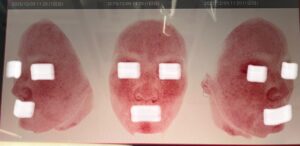

そしてこちら、ルメッカ3回目施術の3週間後に受けた私の肌診断画像です!

青色画像(uv写真)では、隠れたシミ・肝斑や潜在的なメラニンを写しています。

これ、放っておくとほぼ全部シミとして表面化してくる可能性がかなり高いやつです😱

赤色画像では、赤みやニキビ跡等の炎症を表しています。